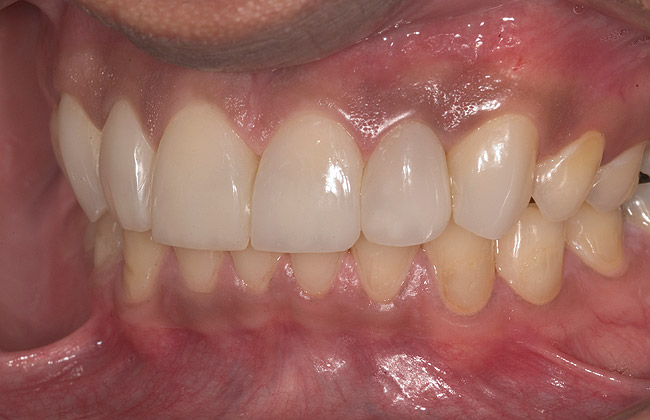

Figure 16  1:2 right lateral view; posteriors discluded in MIP.

Figure 16

Figure 17  1:2 left lateral view; posteriors discluded in MIP.

Figure 17

White enamel shade was placed on the putty index and carried to the palatal surface of No. 9. This layer was spread uniformly and thinned out and spread along the entire width of the tooth (Figure 11). After curing this layer, A2 dentin was layered to simulate the lobular pattern seen in dentin of the natural teeth (Figure 12). After curing, a layer of transparent resin was placed in the incisal areas between the dentinal lobes. The final layer of A2 enamel was built and shaped to full contour (Figure 13). A similar build-up was done for all the remaining anterior teeth. The bite in MIP was adjusted such that there was uniform contact on all anterior teeth. The anterior guidance was harmonized to maintain uniformity in the contact of the incisors during protrusion and the canines and incisors during lateral excursions. Finishing and polishing was done per protocol (Figure 14 through Figure 18).13

The patient was recalled at frequent intervals, and after 8 months, occlusal equilibration was done to harmonize the discrepancy between MIP and CR and to have uniform, stable holding contacts on all posterior teeth and re-confirm that the anterior guidance was adequate to disclude posteriors.